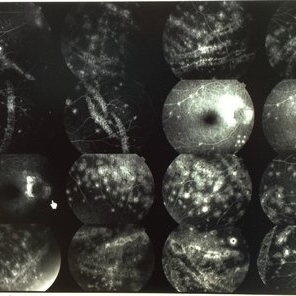

BSCR/HLA-A29+

Jul 1 2014 by John S. King, MD

BSCR/HLA-A29+, MA male, photopsia on p/c, small hypopigmented round to oval lesions mainly peripapillary and inf-nasal to nerve, controlled on cellcept and cyclosporine.

Photographer: Wayne A Ladlee Jr

Condition/keywords: birdshot chorioretinopathy